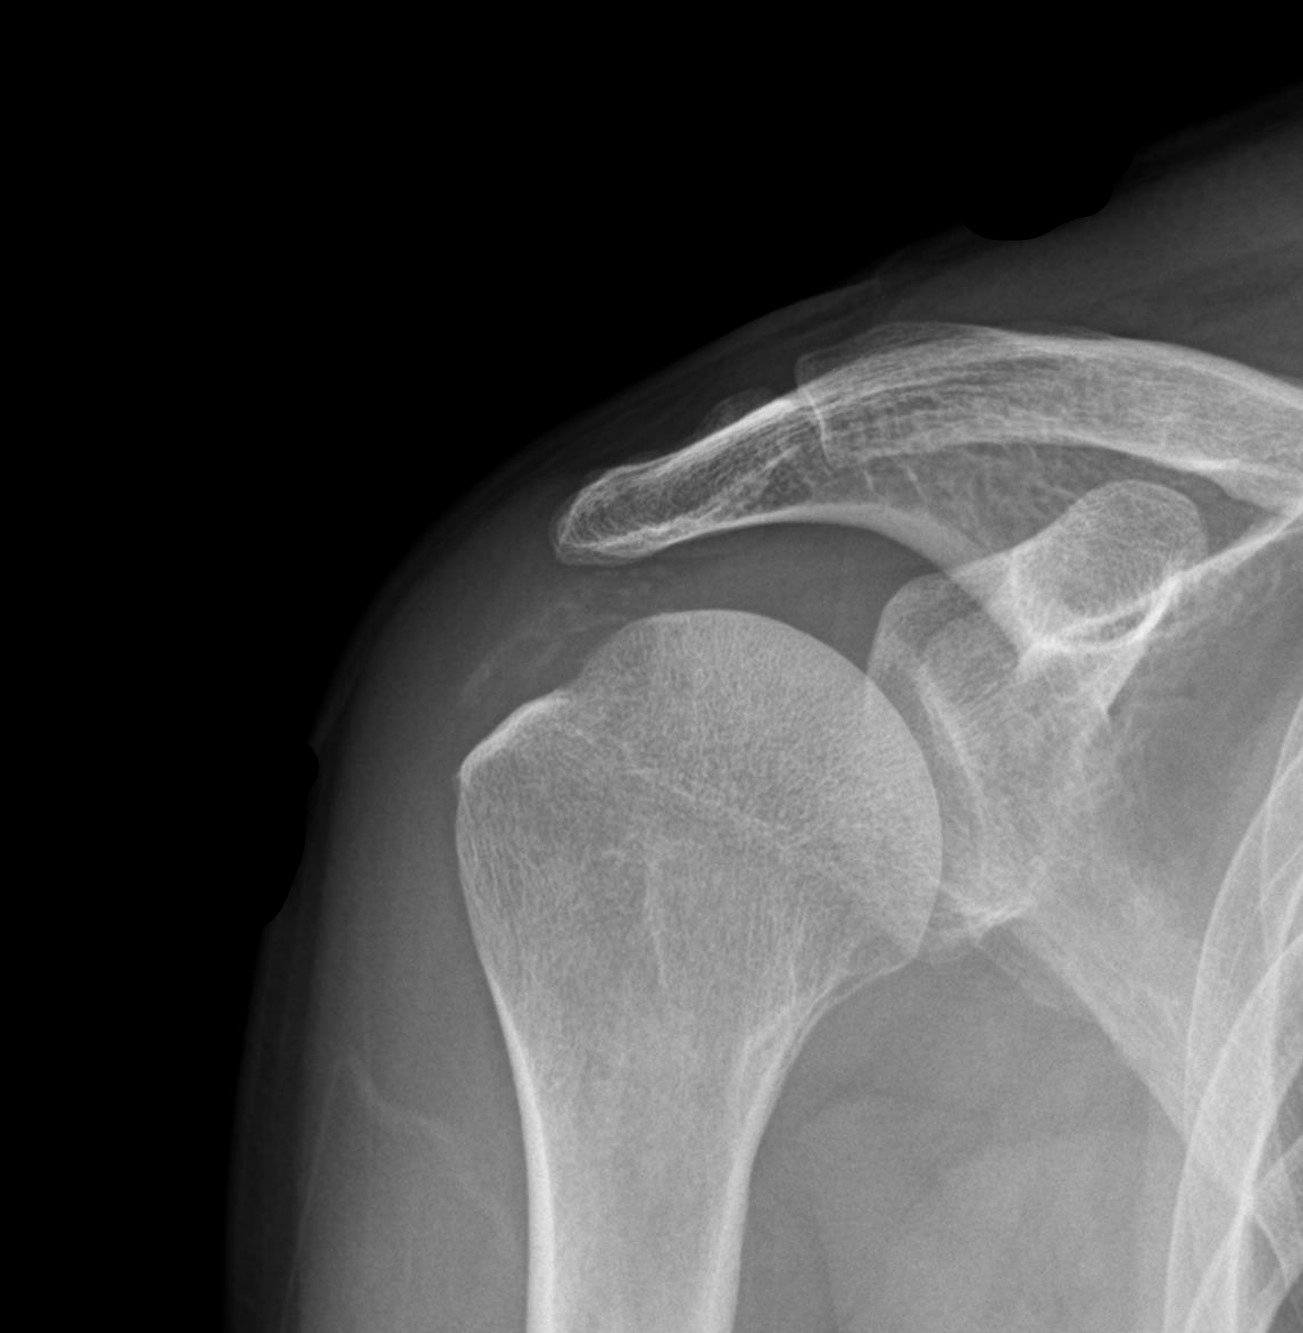

X-ray와 MRI, 초음파 검사를 시행했습니다.

진단 결과:

- ✓석회성건염: 극상건에 약 1.4cm 석회 (휴지기)

- ✓회전근개 관절면측 부분파열: 약 40%

두 가지 문제가 동시에 있었습니다.